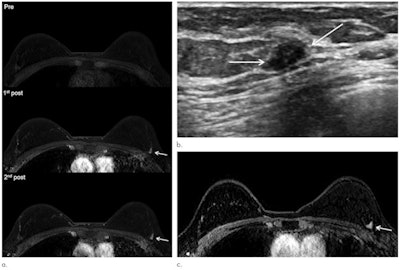

Over the study period, 38 cancers were found; abbreviated screening breast MRI exams identified 29 cancers and missed nine. Of these nine, seven were detected on other imaging modalities and two were interval cancers, for an interval cancer rate of 0.66 per 1,000 exams. All of the nine missed lesions were node-negative, early-stage invasive cancers, according to the group.